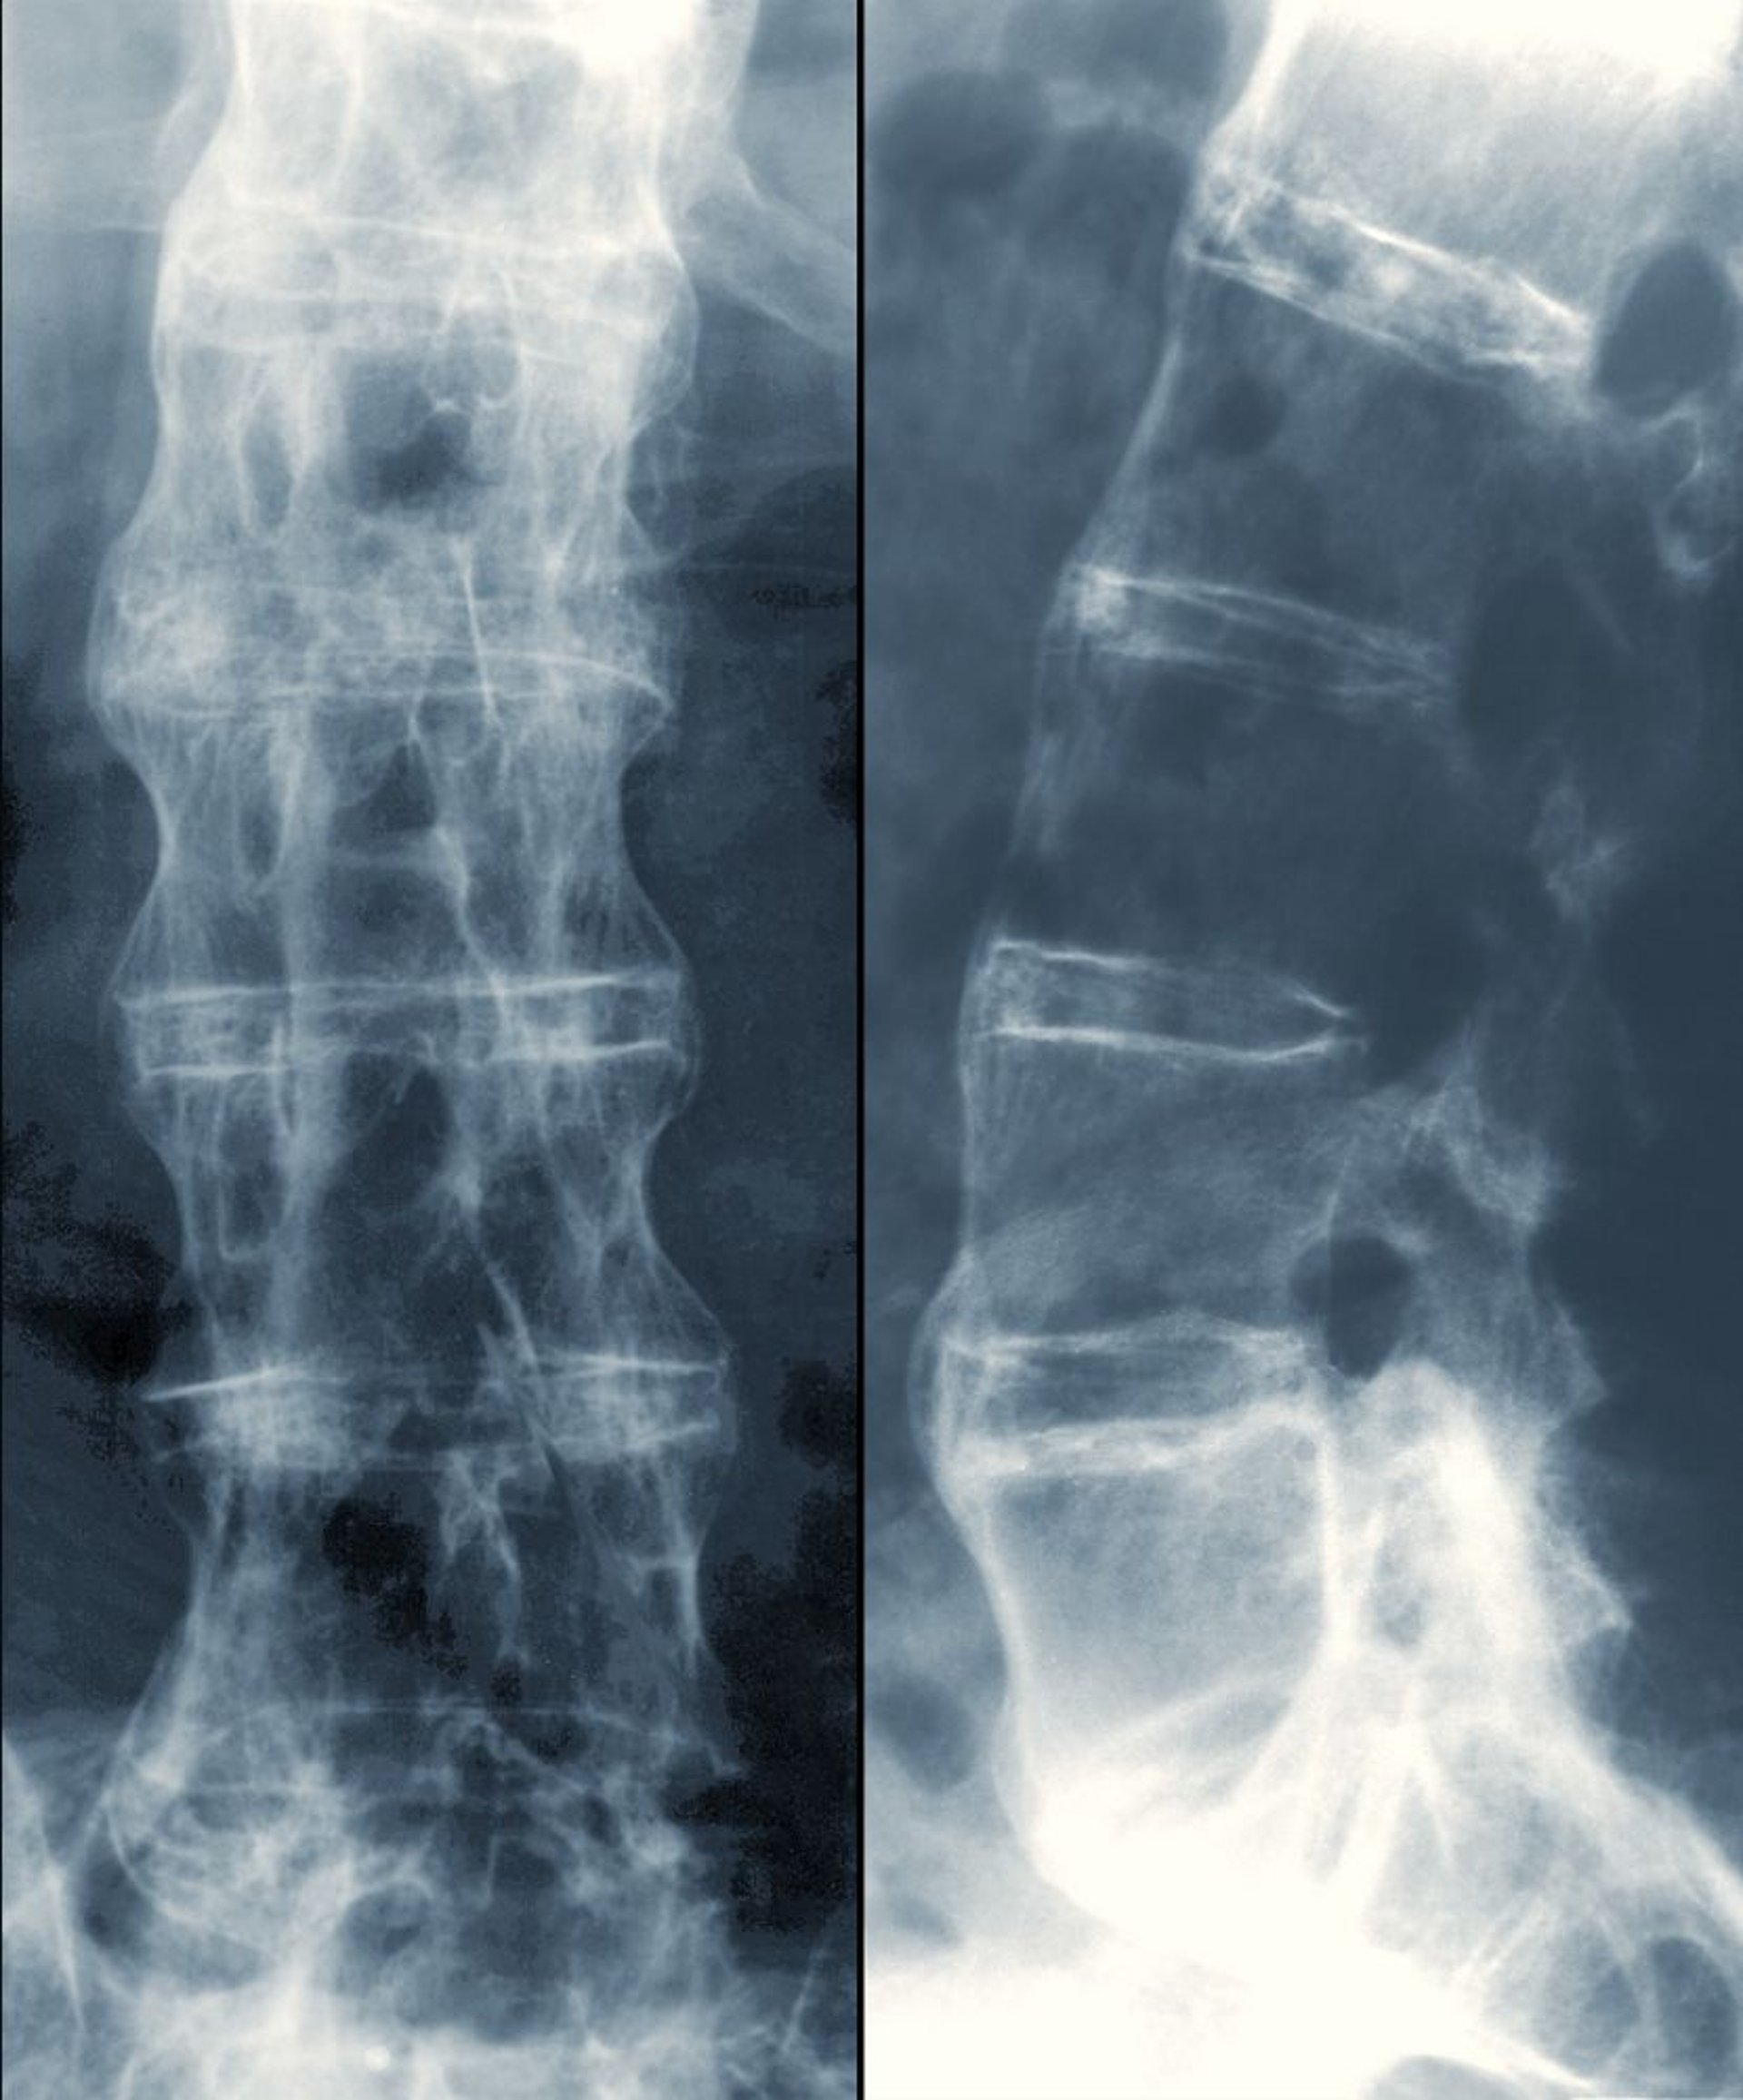

このX線写真には,腰椎間の硬化像,前弯の減弱,および腰椎の癒合という,進行した強直性脊椎炎を示唆する所見が認められる。

DR P. MARAZZI/SCIENCE PHOTO LIBRARY

X線上の最初の異常は,軟骨下のびらんによって生じる仙腸関節の偽の開大であり,硬化または後の狭小化および最終的な癒合が続く。変化は対称性である。脊椎の初期変化は,上位腰椎の角部分の硬化に伴う方形化;斑状の靱帯石灰化(shiny corner sign);および1カ所または2カ所の進行性の靱帯骨棘形成である。後期の変化により「竹様脊柱(bamboo spine)」の外観が呈するが,これは顕著な靱帯骨棘形成,広範な脊椎周囲の靱帯石灰化,および骨粗鬆症に起因する;これらの変化は,一部の患者で平均で10年間かけて発生する。

この強直性脊椎炎患者の脊椎X線写真では,椎骨間に余分な骨(明るい白色)が認められる。癒合が完全な部位では「竹様脊柱(bamboo spine)」の外観を呈する。

ZEPHYR/SCIENCE PHOTO LIBRARY